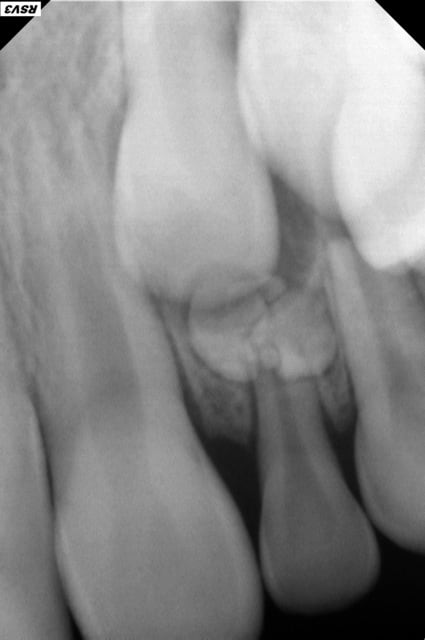

RX 62

Un odontome je pense ...

BBD Enfant de 9 ans .Je me suis étonnée de la presence de la 62 sur l'arcade alors que 12 est en place

Je vais la diriger tout de suite chez l'ortho avant d'extraire, pour eviter la fermeture d'espace.

au fond du canal

Bravo de l'avoir vu avant que le temps continue à jouer en défaveur de cette enfant.